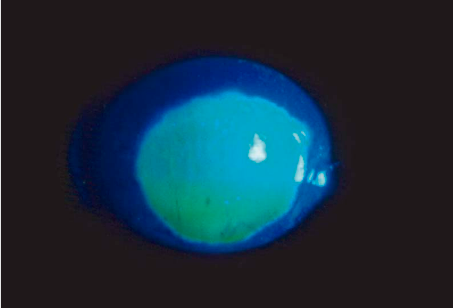

107

Dx

Queratitis por herpes con dendrita